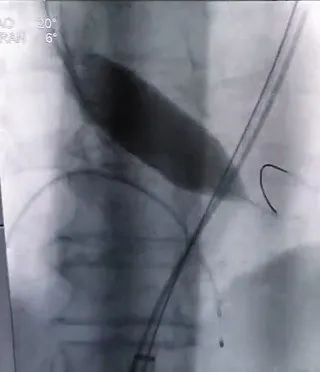

在室速状态下成功释放人工瓣膜

全麻后,成功穿刺右股动脉,通过穿刺点输送系统将瓣膜输送至病变的主动脉瓣处,经过严密地心电监护、心脏食道超声引导,手术团队在心室快速起搏下,使得收缩压降到 60 mmHg、脉压差小于 10 mmHg,此时释放人工生物瓣膜取代自身病变的瓣膜,食道超声检查无瓣周漏,人工瓣膜工作正常,手术完美结束。